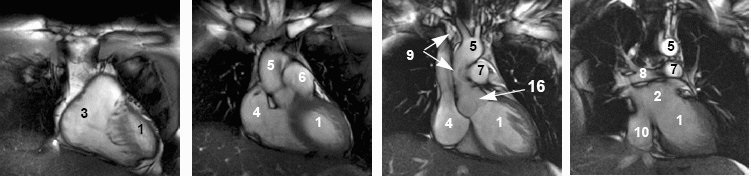

Cardiac anatomy

View an image plane and refer to the legend below for the corresponding cardiac anatomy.

| Cardiac anatomy image legend | |||

|---|---|---|---|

| 1 = left ventricle

2 = left atrium 3 = right ventricle 4 = right atrium | 5 = aorta

6 = pulmonary artery 7 = left pulmonary artery 8 = right pulmonary artery | 9 = superior vena cava

10 = inferior vena cava 12 = right pulmonary vein 13 = pulmonary valve | 14 = tricuspid valve

15 = mitral valve 16 = aortic valve 17 = ventricular outflow tract |